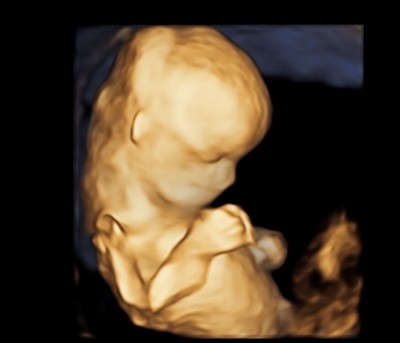

Ale najważniejsze - Dzidzia ma prawie 5 cm, wierciła sie i skakała jak oszalała, wierzgała rączkami i nóżkami